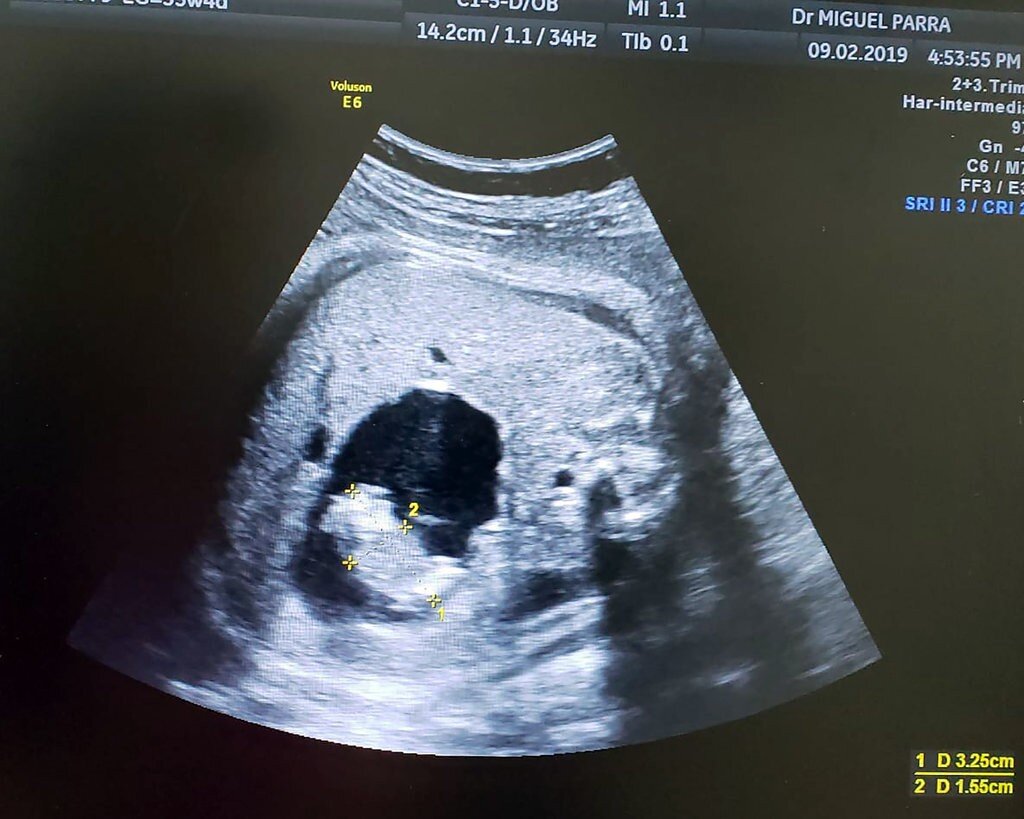

Ультразвуковое исследование, с помощью которого было диагностировано это состояние

Настоящий случай особенно необычен тем, что доктора диагностировали Fetus in fetu еще во время беременности, ошибочно приняв его за печеночную кисту. Но с помощью цветной допплерографии и 3D/4D ультразвука детали стали отчетливее и врачи обратили внимание на структуру, похожую на пуповину, которая соединялась с кишечником старшего близнеца.